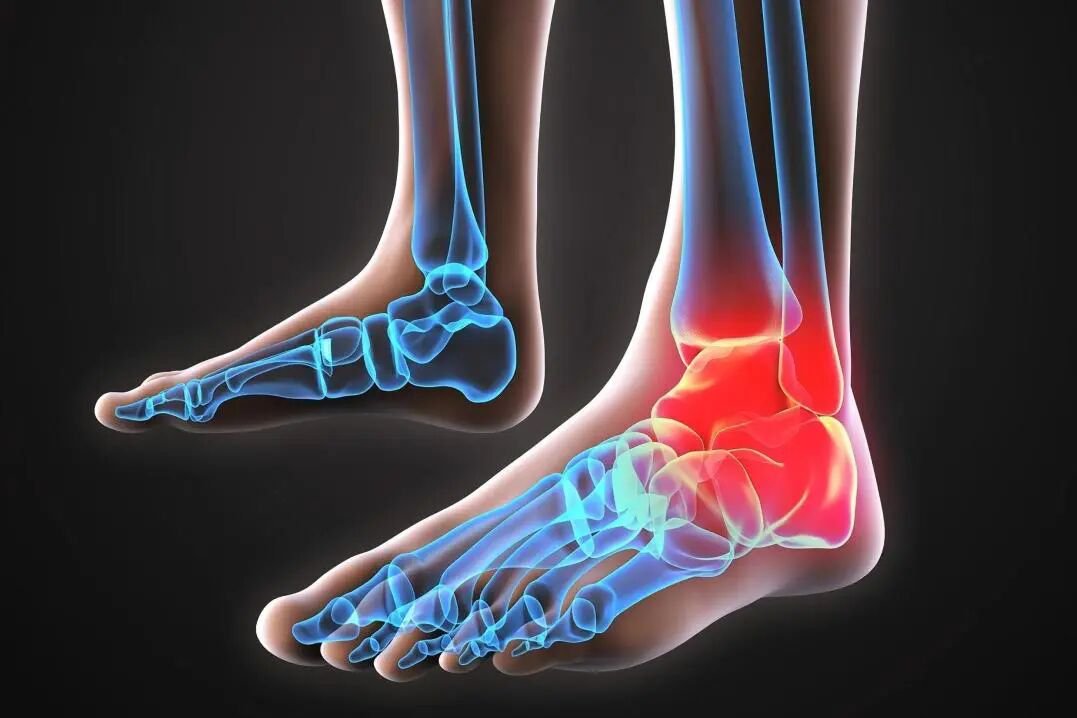

脚后跟疼痛,医学上称为足跟痛,是指足跟一侧或两侧疼痛,是由于跟骨、关节、滑囊、筋膜等处病变引起的疾病。表面上不红不肿,但痛感明显。

引起足跟痛的原因有很多种,下面我们来介绍几个比较常见的情况——

1、足底筋膜炎

正常足弓就像一张弓,足底筋膜就像弓弦,我们每走一步弓弦都会收缩伸展一次,当弓弦收缩的太频繁或拉伸太大时就会受到损伤,从而产生无菌性炎症,引发足底筋膜炎。